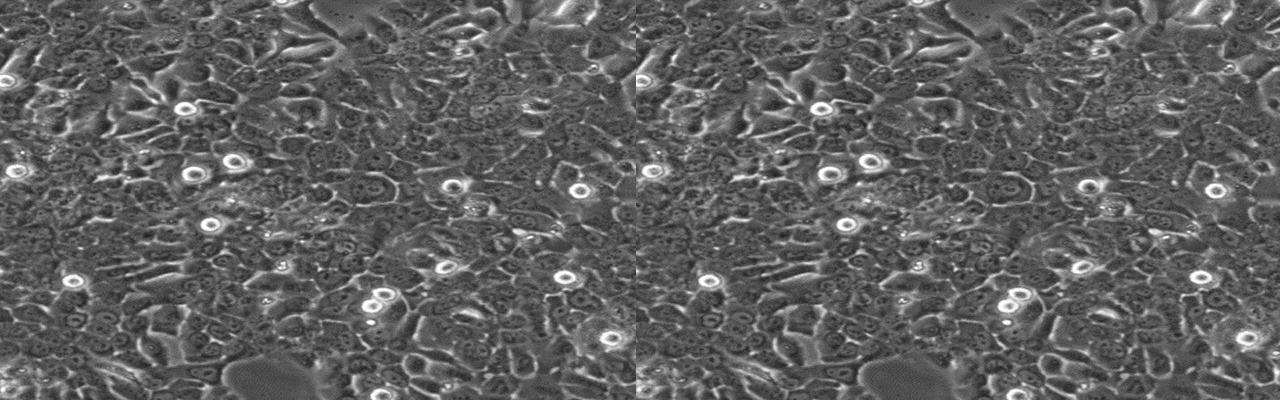

| 细胞全名 | 人喉癌细胞,TU212细胞 |

| 生长特性: | 贴壁生长 |